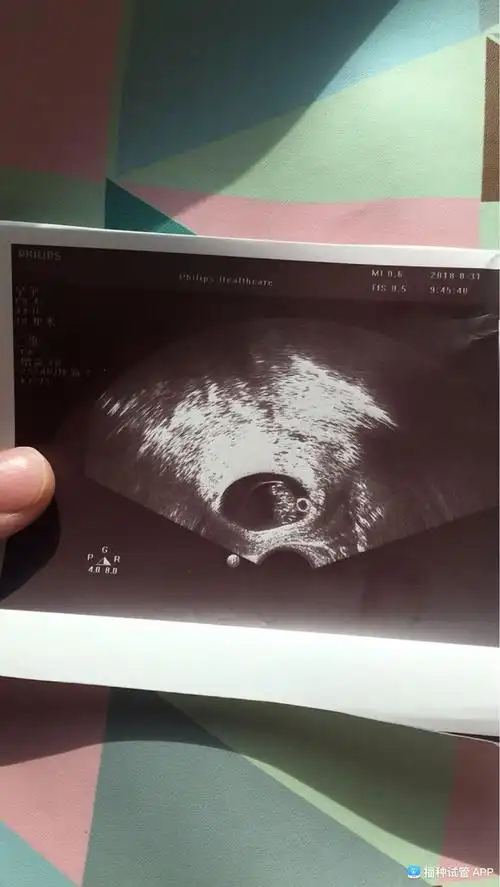

亲们谁会看b超单,8周的b超,孕囊里那个白色小圈圈是啥